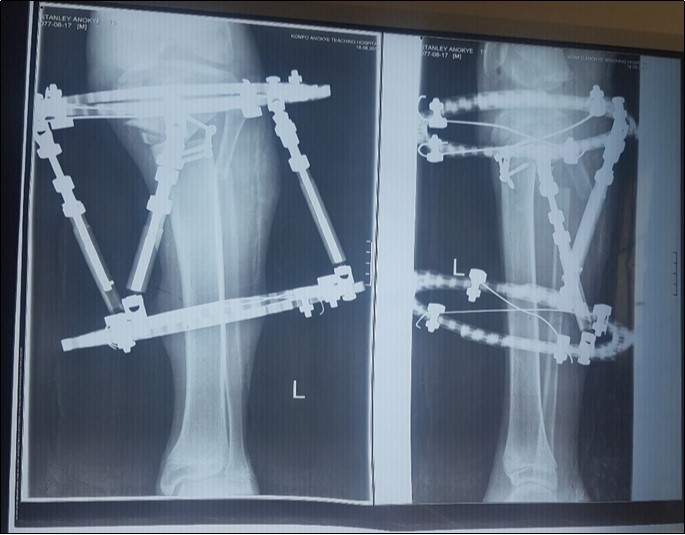

In this report we present our correction procedure for Langenskiold Type VI with a single-stage double tibial osteotomy and maintenance of correction of deformity with a Taylor Spatial Frame. Figure 5, Figure 6.

Figure 6.Post-operative x-ray showing the proximal tibia and the fibula osteotomy as well as the Taylor Spatial Frame.

Post-operative x-ray showing the proximal tibia and the fibula osteotomy as well as the Taylor Spatial Frame.